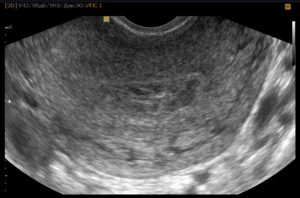

Ультразвуковое исследование и желтое тело

Можно ли заметить плодное яйцо на УЗИ на данном сроке? К сожалению, сейчас еще нет. Даже если проходить обследование влагалищным датчиком, так как оно еще очень маленького размера.

Доктор способен заметить только лишь хороший, пышный эндометрий, типичный для этой фазы месячного цикла, и желтоватое тело в яичнике.

В самом начале ожидания ребенка, УЗИ проводится при помощи трансвагинального датчика. Однако врач-диагност пока сможет лишь предположить, наступила беременность или нет, потому что срок слишком мал для точных формулировок.

При возникновении вопроса, на сколько точно УЗИ определяет срок беременности, следует знать, что все зависит от выбранного способа диагностики. На ранних сроках рекомендуется делать трансвагинальное УЗИ. Оно проводится методом введения во влагалище датчика.

Узи на 1 неделе беременности

Специалисты не назначают УЗИ во время первой недели беременности, так как сам факт изменения положения женщины еще не подтвержден. Женщина даже не будет догадываться о таком маленьком сроке. О беременности как о положении говорят уже после 3-й недели и УЗИ может ее подтвердить начиная с этого срока.